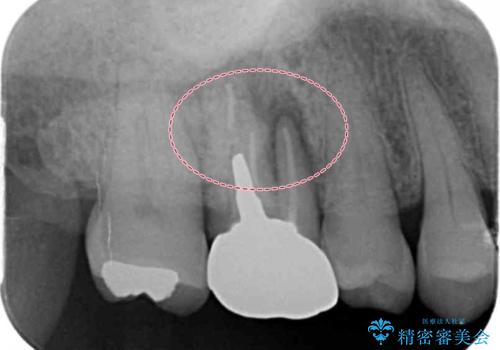

- 症状はないものの、検査の結果右上の奥歯が大きく割れていることが確認されたケースです。

無症状であったため放置していた結果、歯の周囲の骨が溶けてなくなっていました。

歯の深いところまで割れてしまっている場合は健康な状態での歯の保存ができないため抜歯の適応になります。

今回は抜歯後に骨の補填材を足し、適合の良いブリッジを装着していくこととなりました。